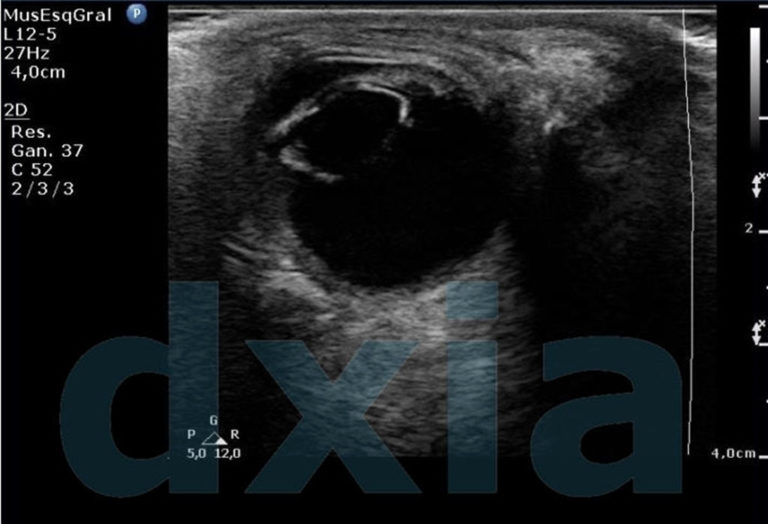

Estudio Ecografía ocular (Modo 2D)

El estudio de ecografía ocular (modo 2D) se realiza con sonda de alta frecuencia. Está indicado para la obtención de...